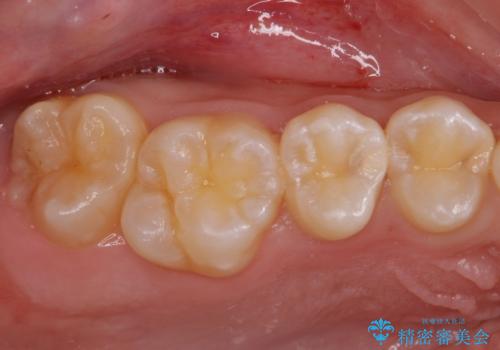

歯と歯の間の虫歯 セラミックインレーでの治療

- 検査の結果奥歯と奥歯の間に虫歯が確認されました。

虫歯を取り除いた後、セラミックインレーで修復していきます。

- 右上45 セラミックインレー 77,000円×2本費用は治療当時の料金となります